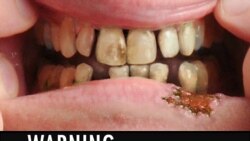

Шестте најголеми тутунски компании во 2010 година заработија над 35 милијарди долари, што е скоро ист профит што заеднички го остварија Кока Кола, Мајкросфт и Мекдоналдс. Пушењето предизвикува рак на белите дробови, како и неколку други хронични дишни заболувања и е голем ризичен фактор за срцевите заболувања. Повеќе од 170 земји ја имаат потпишано конвенцијата на Светската здравствена организација со која се обврзуваат на мерки за ограничување на пушењето.

Шестте најголеми тутунски компании во 2010 година заработија над 35 милијарди долари, што е скоро ист профит што заеднички го остварија Кока Кола, Мајкросфт и Мекдоналдс. Пушењето предизвикува рак на белите дробови, како и неколку други хронични дишни заболувања и е голем ризичен фактор за срцевите заболувања. Повеќе од 170 земји ја имаат потпишано конвенцијата на Светската здравствена организација со која се обврзуваат на мерки за ограничување на пушењето.